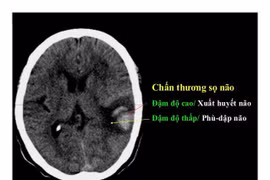

(khoahocdoisong.vn) - Chấn thương sọ não nặng được điều trị bằng phẫu thuật, hồi sức hoặc phối hợp. Kết quả hồi sức và điều trị bệnh nhân chấn thương sọ não nặng phụ thuộc vào nhiều yếu tố như tuổi, tình trạng bệnh nhân, tổn thương tại não, tổn thương phối hợp, thời điểm điều trị.

(khoahocdoisong.vn) - Chấn thương sọ não thường bắt nguồn từ các loại chấn thương về não bao gồm chảy máu, chấn động mạnh, rung động não hoặc não bị bầm.